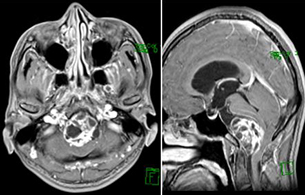

症例2) 38歳女性、左三叉神経鞘腫、外科治療のみ

< 画像所見 >

右三叉神経部に大きな腫瘍あり。

< 手術所見 >

ナビゲーションシステムの使用

< 術後画像所見 >